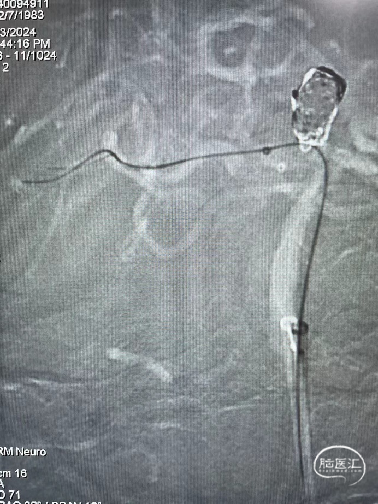

DSA:右侧P1段一6.8*9.7mm不规则囊状突起动脉瘤,远端P2段呈螺旋状蛇形动脉瘤改变。

DSA:右侧P1段一6.8*9.7mm不规则囊状突起动脉瘤,右侧A1段动脉瘤。夹层蛇形动脉瘤。

DSA:评估右侧后交通。

右侧颈内正位

右侧颈内3D

椎动脉压颈3D

术后即刻复查:远端血管通畅、支架打开良好。

术后正位复查